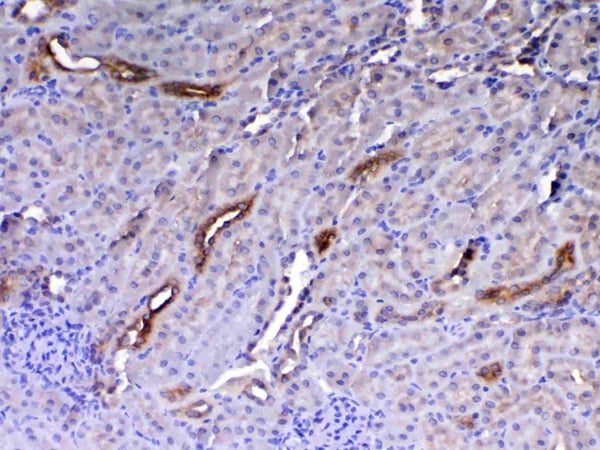

VEGF Receptor 3, Polyclonal Antibody (Cat# AAA19146)

VEGF Receptor 3, Polyclonal Antibody (Cat# AAA19147)